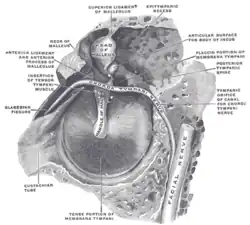

A membrana timpânica direita com o martelo e a corda do tímpano, vista de dentro, por trás, e de cima. (Martelo visível no centro.) | |

Orelha externa e média, abertas pela frente. Lado direito. Cadeia de ossículos e seus ligamentos, vistos de frente em uma seção transversal vertical do Tímpano.

Cadeia de ossículos e seus ligamentos, vistos de frente em uma seção transversal vertical do Tímpano. CT imagem de martelo.